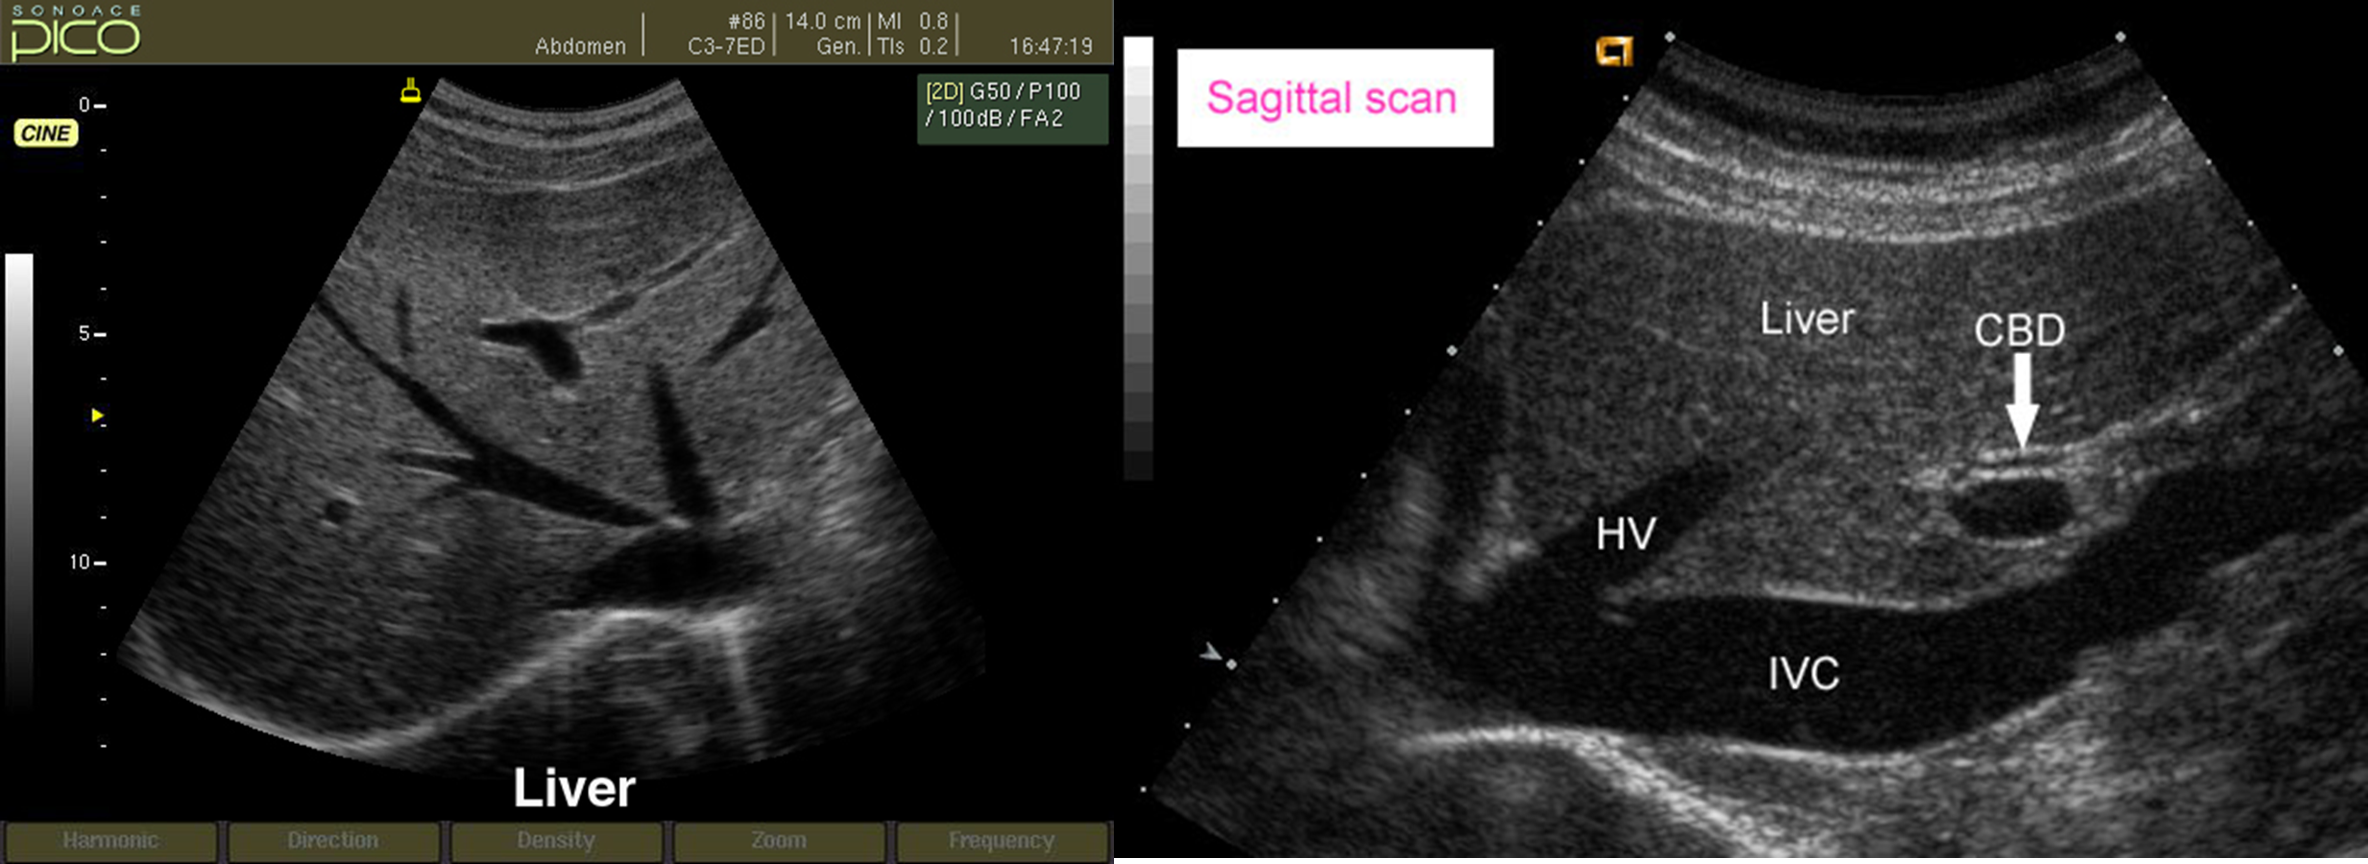

Ultrasound is the initial investigation for demonstrating the GB and bile ducts. , it is the next best step for patients with suggestive clinical features, risk factors for cholelithiasis, and cholestatic.

The common bile duct is seen as a small, tubular structure lying anterior to the portal vein in the porta hepatis and should not measure more than 7 mm in diameter unless the patient has had a cholecystectomy, when it may be larger.